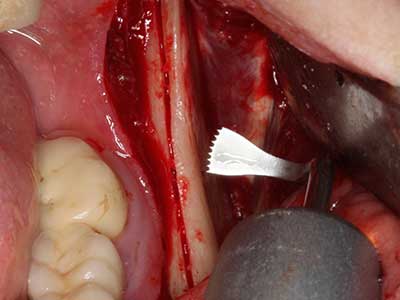

Indication: Preparations close to nerve tissue

As noted above, indications for piezo surgery can also be found in the field of conservative dental surgery. Special working tips simplify the exposure of root tips and make it easier to protect nerves and sinus mucous membranes, particularly in the lower premolar and upper posterior tooth regions. Angled diamond tips are used to precisely prepare the resection cavity for the retrograde root filler material for unsealed apical obturation. The ultrasonic technology means the tips can be very slender, which improves the view and the size of the access cavity. As a result, the application of ultrasonic surgery for this indication is one of the standard procedures for apical resection (Del Fabbro, Tsesis et al. 2010, Scarano, Artese et al. 2012).

Indication: Apical resection

When surgical procedures are performed on bone in the immediate vicinity of sensitive structures such as blood vessels or nerves, rotary instruments pose a significant risk of iatrogenic injury. Piezoelectric devices can be helpful for preparation of bone covers and removal of hard tissue close to nerves, particularly for exposure of nerves after iatrogenic injury but also during nerve lateralization for resective and reconstructive procedures or implant placement (Fig. 17-20). Light contact between the piezotip and the nerve does not generally result in damage but proceeding incautiously with saw-like motions or attachments where a residual bone substrate remains may cause temporary or even permanent nerve damage. However, the risk of damage is considered to be substantially lower than when using saws or milling instruments (Pereira, Gealh et al. 2014).